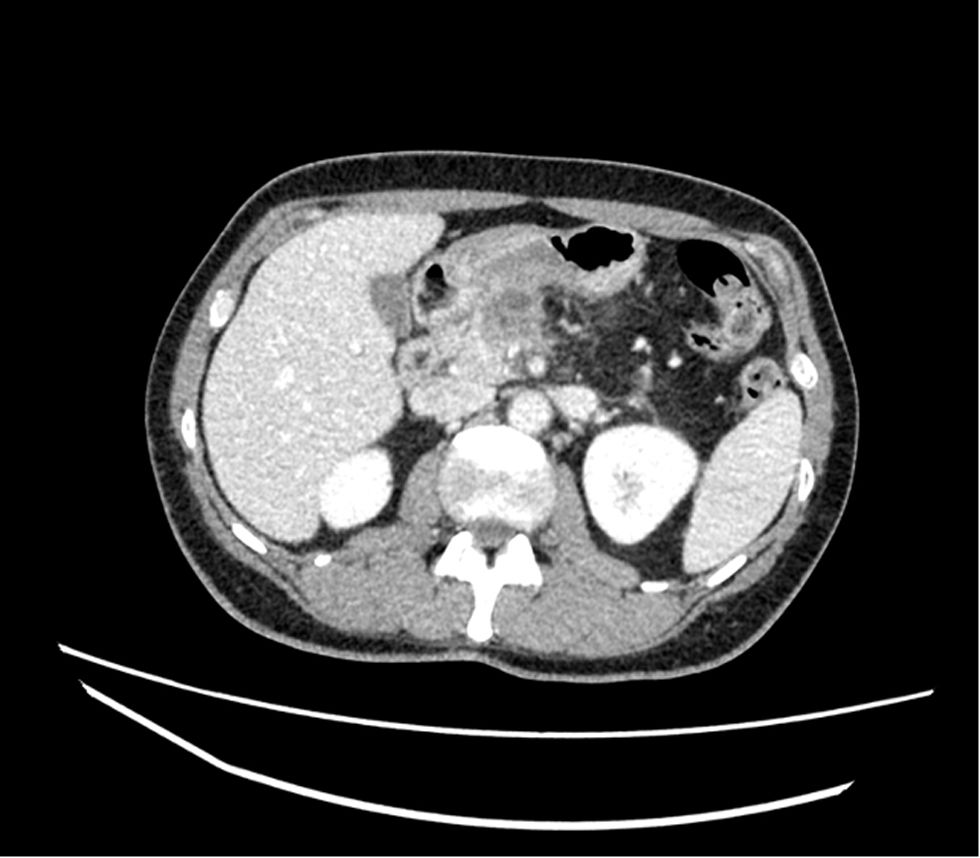

Técnica quirúrgica (vídeo cirugía)El uso de shunt íleo-cava transitorio se indicó en un paciente de 45 años afecto de adenocarcinoma de páncreas localmente avanzado que condicionaba una severa colateralidad venosa, con mutación BRCA2; tras recibir 11 ciclos de neoadyuvancia con esquema FOLFIRINOX, con buena tolerancia. Finalizado este, se realizó estudio mediante tomografía computarizada (TC) toraco-abdominal, PET/TC, y resonancia magnética nuclear (RNM), descartando afectación a distancia. Tras presentar el caso en comité multidisciplinario se planificó la intervención con ayuda de estudio 3D13 (figs. 1, 2, 3 y 4)(https://www.cellams.com). En el estudio preoperatorio se evidenció lesión pancreática con afectación del confluente venoso EMP con extensión hasta la confluencia de dos venas ileales (Vil1 y Vil2) y yeyunal (VYy), y contacto con la arteria mesentérica superior (AMS). La afectación de toda la extensión de la vena mesentérica superior (VMS) comportaba la imposibilidad de la anastomosis con seguridad.

Posoperatorio inmediato y análisis anatomopatológico. El posoperatorio transcurrió sin incidencias, se realizó un TC abdominal de control a los cinco días (fig. 8), y fue dado de alta el día 7 posoperatorio sin complicaciones. El análisis anatomopatológico evidenció un adenocarcinoma pancreático de 2,5cms de diámetro invasión vascular de vaso de pequeño calibre e invasión de la capa adventicia de la VMS, márgenes venosos y quirúrgicos libres; sin infiltración perineural, 0 ganglios afectos de 30 analizados, ypT1ypN0 R0 (UICC8aEd), grado regresión GRT 2 (respuesta parcial), Grado regresión Evans GIIa.

Respecto al caso presentado, en primer lugar, el estudio tres dimensiones fue imprescindible para planificar la cirugía. Una vez evidenciada la afectación del confluente EPM, de las venas yeyunal e ileal, y el contacto con la AMS; planificamos una esplenopancreatectomía total con resección venosa de larga longitud. Ante este escenario, optamos por disecar el campo quirúrgico craneal y caudalmente al tumor identificando los vasos afectos. Un detalle importante fue preservar la vena yeyunal dado su diámetro, anastomosándola a la vena ileal; a pesar de ser una vena frágil y que en ocasiones se aconseja sacrificar para evitar problemas con su reconstrucción23. Decidimos realizar un shunt intraoperatorio que permitiera progresar en la disección de la AMS, VMS y en la disección del cuerpo-cola pancreático. Una vez desclampado el shunt íleo-cava el campo quirúrgico se mantuvo exangüe, y el flujo hepático se mantuvo a través de la arteria hepática y la vena esplénica y el confluente portal. Finalmente, el estudio anatomopatológico evidenció una resección R0.